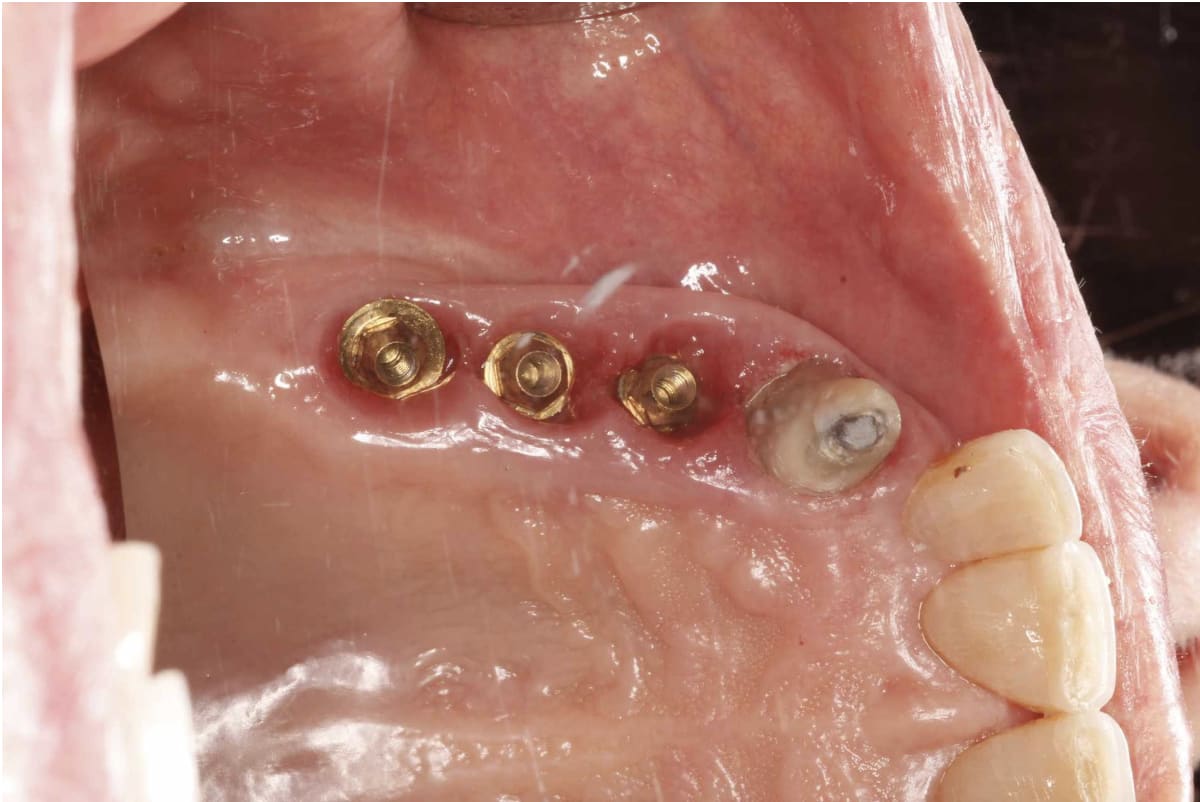

J'ai pu déposer les couronnes avec un tournevis hex 1,2 (type camlog) et j'arrive sur 3 piliers multi unit en or je pense.(cf photo).

A priori ce praticien a posé plusieurs marques d'implants (Straumann victory tbr ankylos) et je pense qu'il s'agit de dentium. Pour m'en assurer j'ai fait une recherche par spot implant qui me le confirme. Probleme : j'ai contacté dentium leur ai envoyé les photos en leur demandant de me confirmer mon hypothèse et éventuellement de me donner le modèle d'implant pour commander l'accastillage et les scanbodies pour piliers MU. reponse de Dentium : "ce n'est pas un implant dentium crdt" je leur ai demandé d'argumenter car cela y ressemble et je n'ai actuellement aucune réponse (je pense que la photo des piliers MU les a fait shifter) donc avant de commander par moi meme je voulais avoir un avis de poseur dentium.

clairement des dentium....

mais le plus à gauche doit être une première génération

C'est pas de l'or, c'est anodisé doré.....et c'est pour l'esthétique, meilleur mimétisme pour les gencives, çà évite un effet grisâtre du pilier titane....